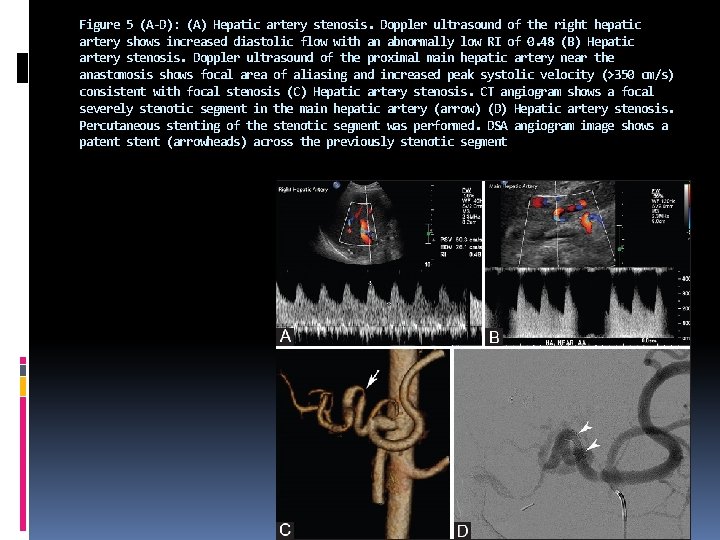

Figure 5 (A-D): (A) Hepatic artery stenosis. Doppler ultrasound of the right hepatic artery shows increased diastolic flow with an abnormally low RI of 0. 48 (B) Hepatic artery stenosis. Doppler ultrasound of the proximal main hepatic artery near the anastomosis shows focal area of aliasing and increased peak systolic velocity (>350 cm/s) consistent with focal stenosis (C) Hepatic artery stenosis. CT angiogram shows a focal severely stenotic segment in the main hepatic artery (arrow) (D) Hepatic artery stenosis. Percutaneous stenting of the stenotic segment was performed. DSA angiogram image shows a patent stent (arrowheads) across the previously stenotic segment